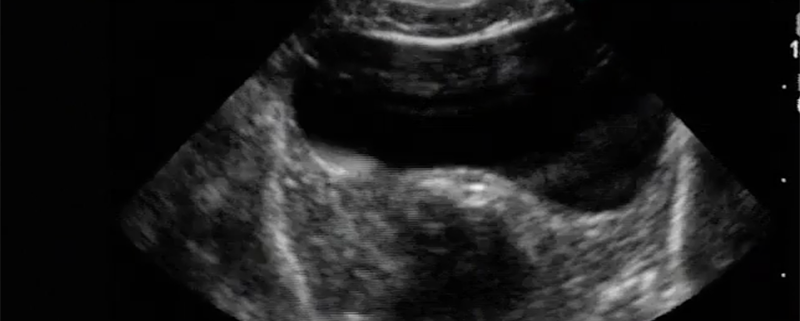

Protegido: Ecografía abdominal 2